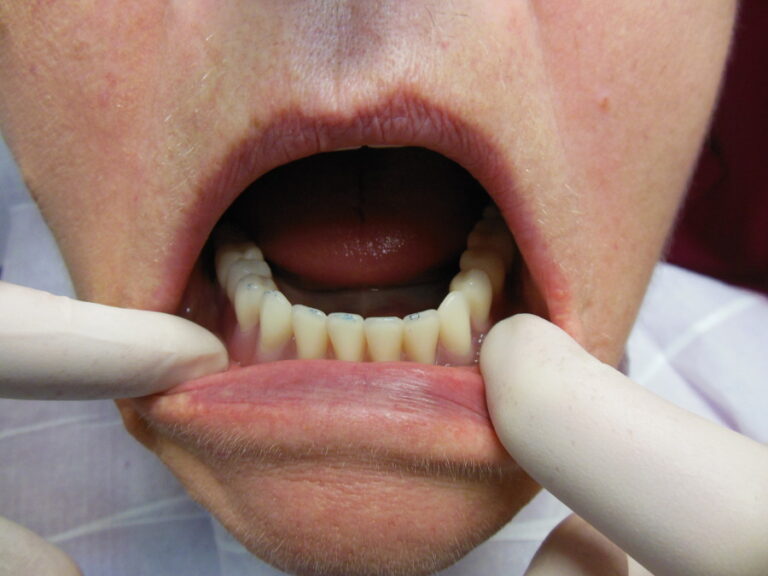

Ortodoncja CBCT

Leczenie chirurgiczno-ortodontyczne wad zębowych z zastosowaniem tomografii spiralnej CBCT w naszej klinice.